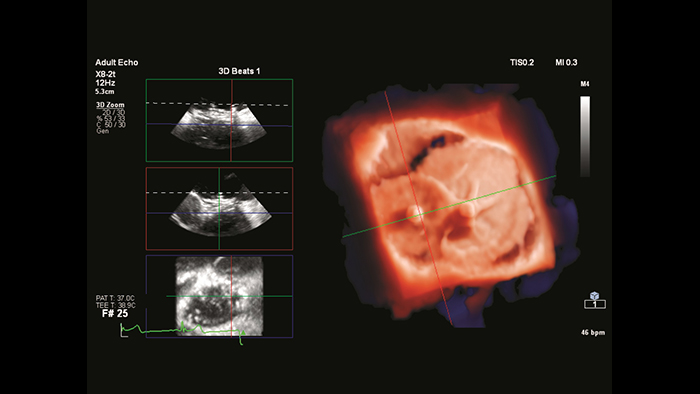

EchoNavigator heart model segmentation

ASD closure with EchoNavigator live fusion